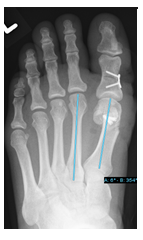

Minimal invasive Fußchirurgie - Metatarsalgie

Die Überlastung der Mittelfußknochen ist oft eine Folge einer Fehlstellung der Großzehe (Hallux valgus) oder eines Sichelfußes. Hierbei sind die betroffenen Mittelfußknochen in der Regel zu lang.

Wenn es bereits zu schmerzhaften Schwielen der Fußsohle kommt, ist eine operative Korrektur auch dieser Knochen notwendig (sogenannte DMMO: distale minimalinvasive metatarsale Osteotomie). Hierzu erfolgt über einen Schnitt von ca. 2-3mm eine Durchtrennung des Knochens. Die Vollbelastung im Anschluss an die Operation führt zu einer Neuausrichtung der durchtrennten Knochen. Da die durchtrennten schmerzhaften Mittelfußköpfchen über Bänder und die Kapsel noch verbunden sind, verwachsen die Knochen in der anatomisch korrekten Position nach ca. 6 Wochen. Innerhalb dieser Zeit kann der Patient mit einem speziellen Schuh voll auftreten, was nur selten schmerzhaft ist. Im Anschluss ist meistens Physiotherapie sinnvoll.